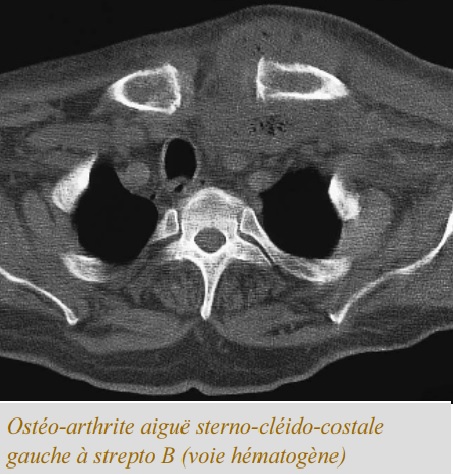

Image radiologique TDM d'une

osteo-artrite aigue sterno-cleido-costale gauche à

streptoccocus Beta hemolytique avec aspect de

erosives oedemateuse hypodense sous chondrale et

image de tumefaction isodense de la region articulo

sterno-claviculaire gauche . |